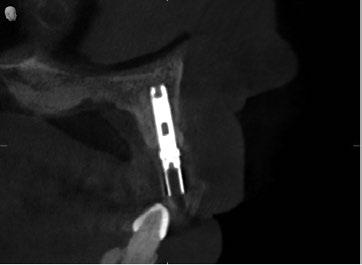

Dos años después de la colocación de esta nueva restauración, observamos que el nivel óseo, que se había mantenido estable durante 17 años, mostraba una mejora notable tras la colocación del nuevo pilar y la nueva corona. Este cambio se aprecia claramente al comparar las radiografías de 2005 con 2007, situación que se ha mantenido hasta la actualidad. (Fig. 11) Es muy probable que el cambio óseo observado se deba a que, para la nueva restauración, se utilizó un pilar mecanizado mediante

maquinaria de precisión en zirconio (Procera), lo que permitió reducir significativamente el espacio en la interfase pilar-implante (gap). Asimismo, no es descartable que a este cambio también haya contribuido la disminución de los micromovimientos del pilar sobre la cabeza del implante, al haberse utilizado un tornillo TorqTiite (Nobel Biocare) ajustado con llave dinamométrica a 35 Ncm, en lugar de hacerlo manualmente a 10–15 Ncm, como se había realizado con el pilar original de Jemt.